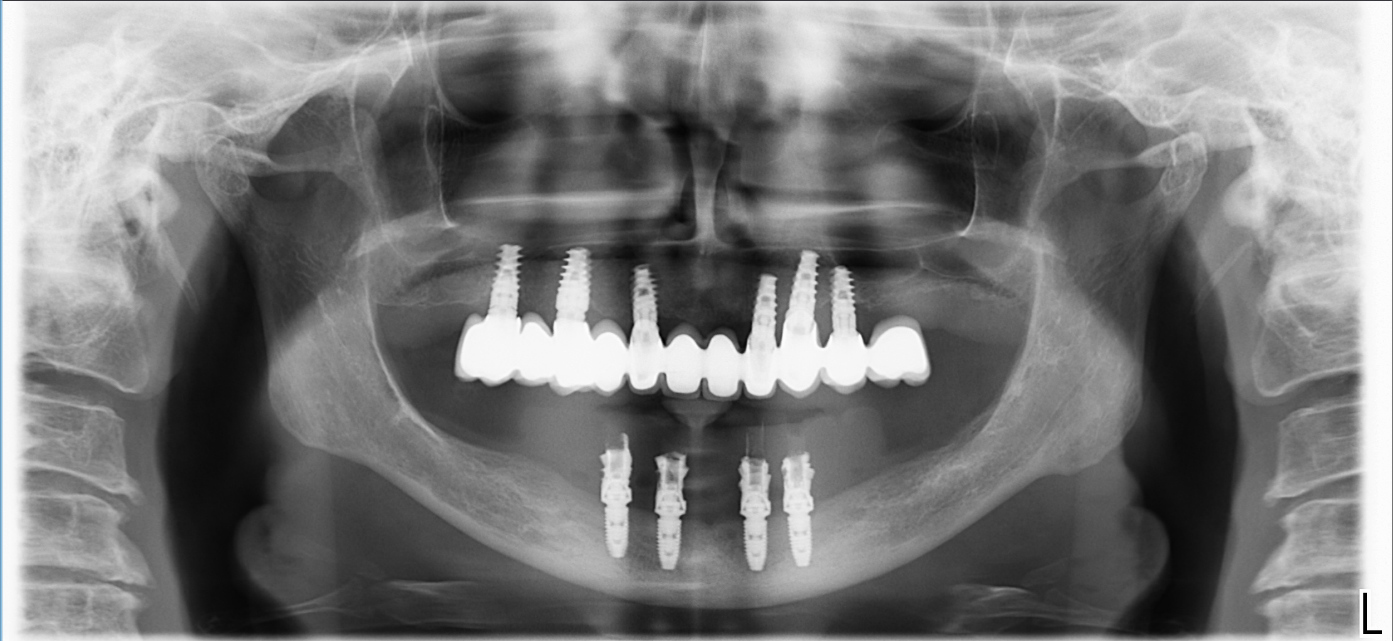

Ovviamente l’intervento è andato alla grande. In poche ore la paziente ha avuto i suoi “nuovi denti fissi” provvisori, dopo un intervento di una quarantina di minuti.

Dopo tre mesi l’ho rivista per le impronte definitive e dopo la prova di ieri tra due settimane andremo in consegna con il definitivo.

Stefano, pur non avendo mai fatto un intervento del genere e pur avendo messo il suo ultimo impianto forse sette anni fa, non ha avuto alcun dubbio nel proporre la soluzione alla signora, semplicemente perché sa che “in mandibola l’all-on-4 si può sempre fare”.